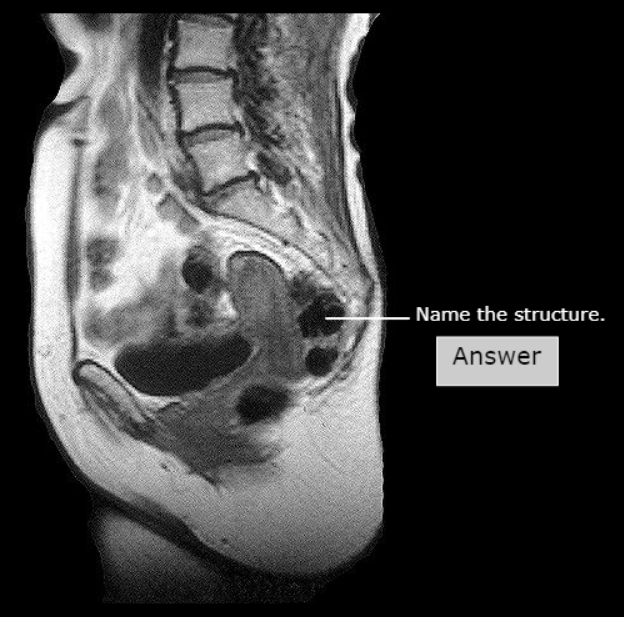

Body of Uterus

Fundus of Uterus